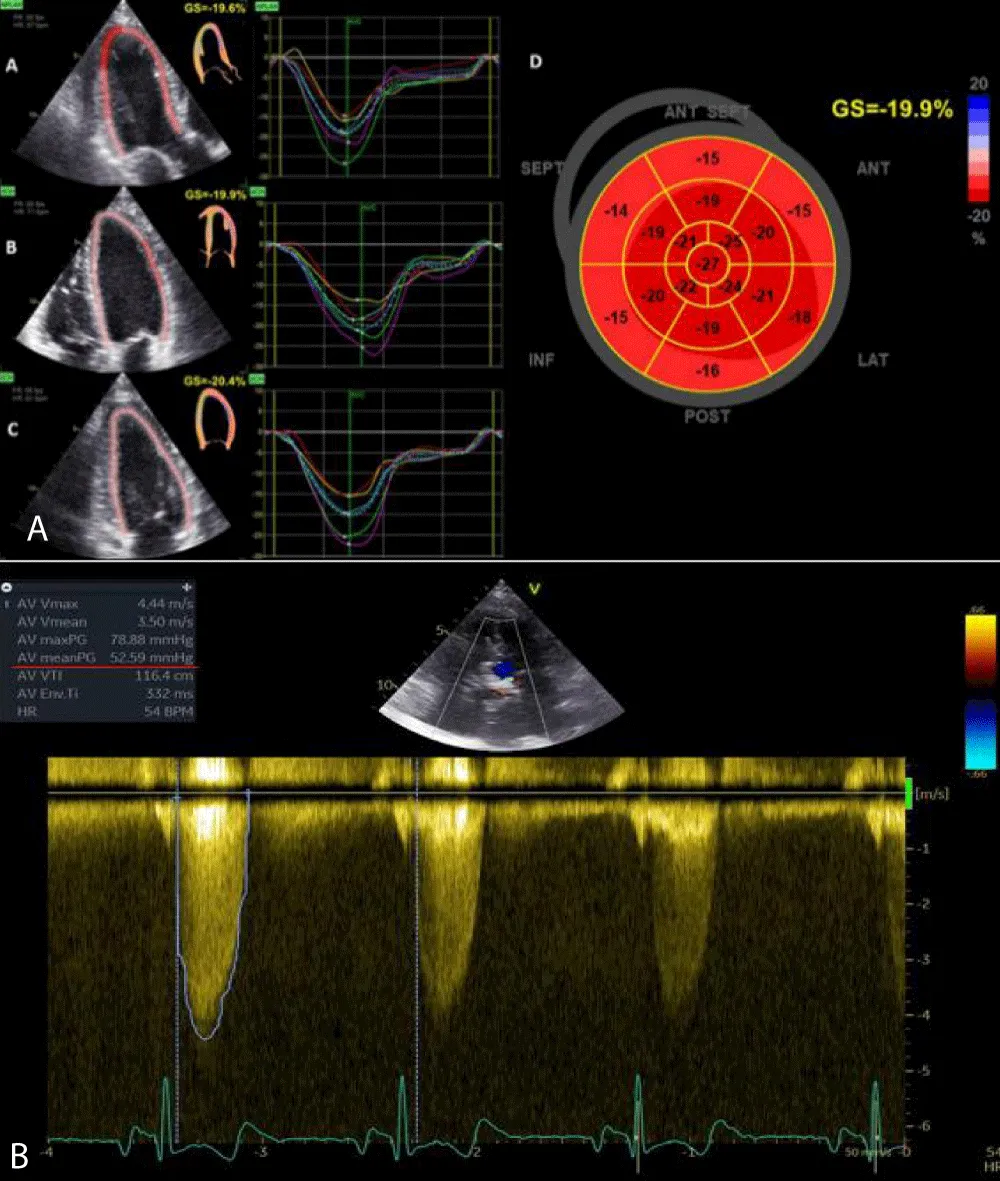

• Cine Steady State Free Precession (SSFP) sequences, ideal for functional cardiac studies (Figure 2)

Download Image

Figure 2: SSFP four chambers, in systolic phase.

• Additional SSFP sequences in order to study the aortic valve plane (to study its morphological characteristics and to calculate the AVA) (Figures 3A and 3B)

Figure 3: Coronal-axial valve aortic planes show a jet of anterograde turbulent flow (3A) and stenotic area (3B).